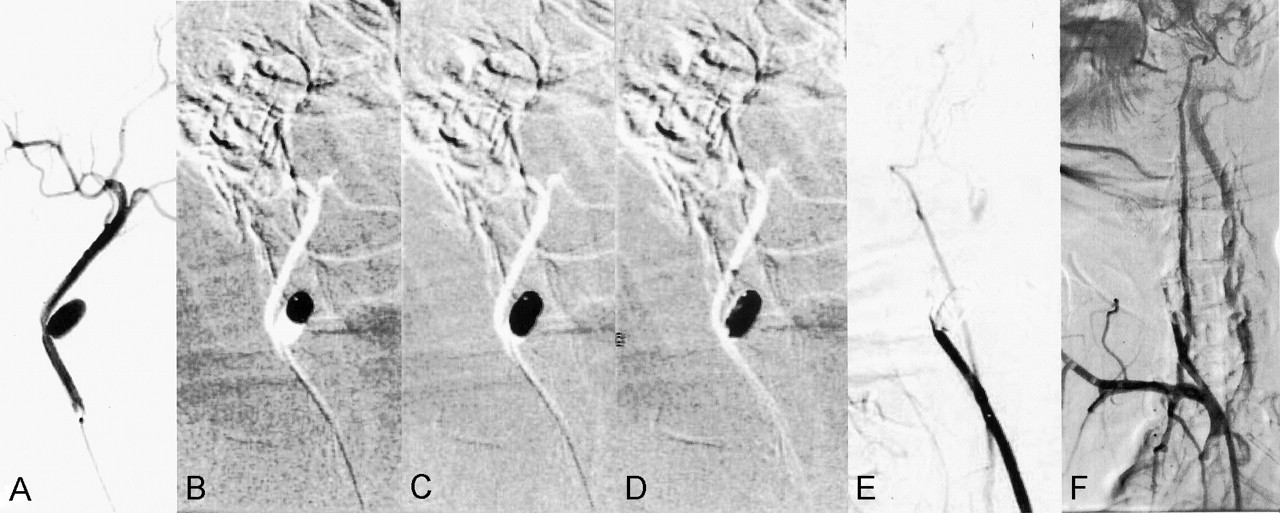

Aneurysm 4. Partially embolized aneurysm without a coil framework.

A, After obtaining this preembolization angiogram, 40% glue was injected for 1 minute and 26 seconds under subtracted, real-time road-map fluoroscopy.

B–D, Frozen images of the early (B), middle (C), and late (D) phases show leakage of the cast along the wall.

E and F, Angiograms obtained immediately after embolization (E) and at 2-month follow-up (F) show persistent occlusion of the carotid artery.